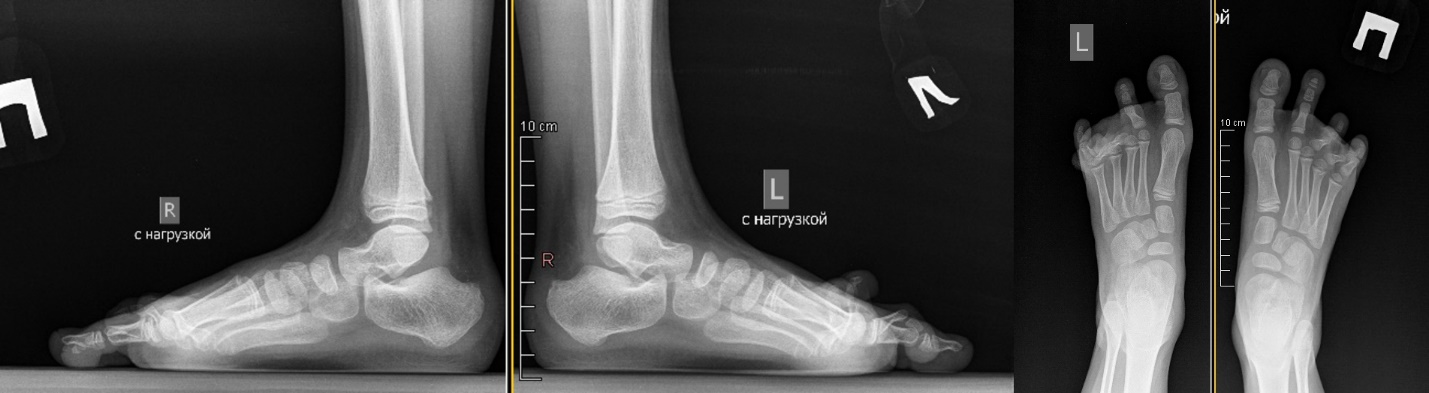

Physical examination of the patient revealed coarse hypertrophic scars on the dorsum of the feet and the lateral surface of the tibiae. The scars were moderately painful at palpation. Evident bilateral desmogenic extension contracture of the third, fourth, and fifth toes in MTPJs was clinically observed in conjunction with flexion contracture of toes in interphalangeal joints. The range of motion in MTPJs was 10-15°. Radiological findings complied with the clinical presentation.

Fig 2. Radiography of the feet before surgery